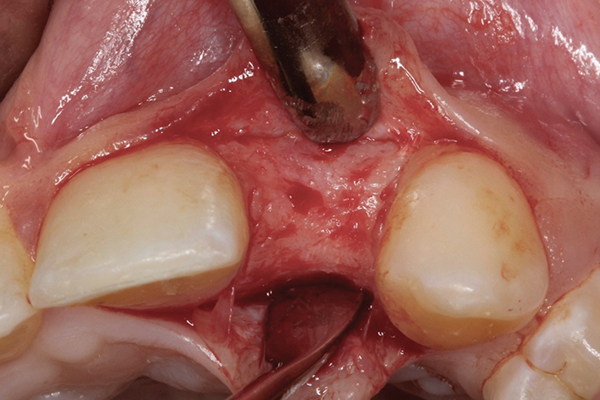

Fig 9 and Fig 10. An implant placed in site No. 10.

When the patient was 18 years old, an implant was placed in site No. 10 with no complications (Figure 9 and Figure 10). Three months later, a periapical radiograph was taken, the implant was torque tested, and a healing abutment (3 mm by 4 mm by 4 mm) was placed.